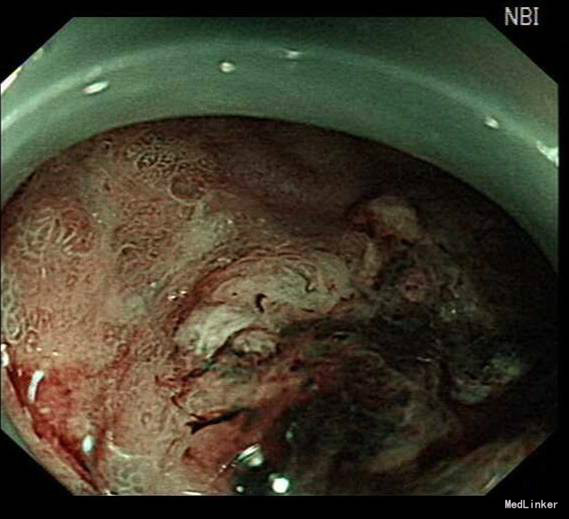

诊疗经过:入院后经过术前检查,行放大内镜检查和超声内镜检查,超声内镜提示:胃窦病灶未突破粘膜下层,诊断考虑:胃早癌。于10月30日行内镜下胃ESD术,术顺,安返病房。经过过制酸、补液等对症处理,3天后患者顺利出院。

随访:出院后2周,电话随访患者,一般情况良好,无不适主诉。 讨论:该患者胃镜见一胃窦前壁粘膜隆起,表面粘膜粗糙,病理示:慢性萎缩性胃炎,伴部分腺体中重度不典型增生,局灶重度不典型增生,超声胃镜病灶未突破粘膜下层,有胃ESD手术指征,故行全麻下胃ESD术。术后病理:胃窦前壁肿瘤:腺上皮高级别上皮同瘤,部分癌变,病变大小1.5*1.1*0.3cm,基底及切缘未见癌。说明手术成功,切缘及基底均无肿瘤侵及。对于早癌患者我们完全可以通过采用ESD方法治愈患者,胃镜下切除早癌较腹腔镜创伤更小。我和患者解释时是这样说的:腹腔镜是微创,而我们内镜下ESD则是微微创。